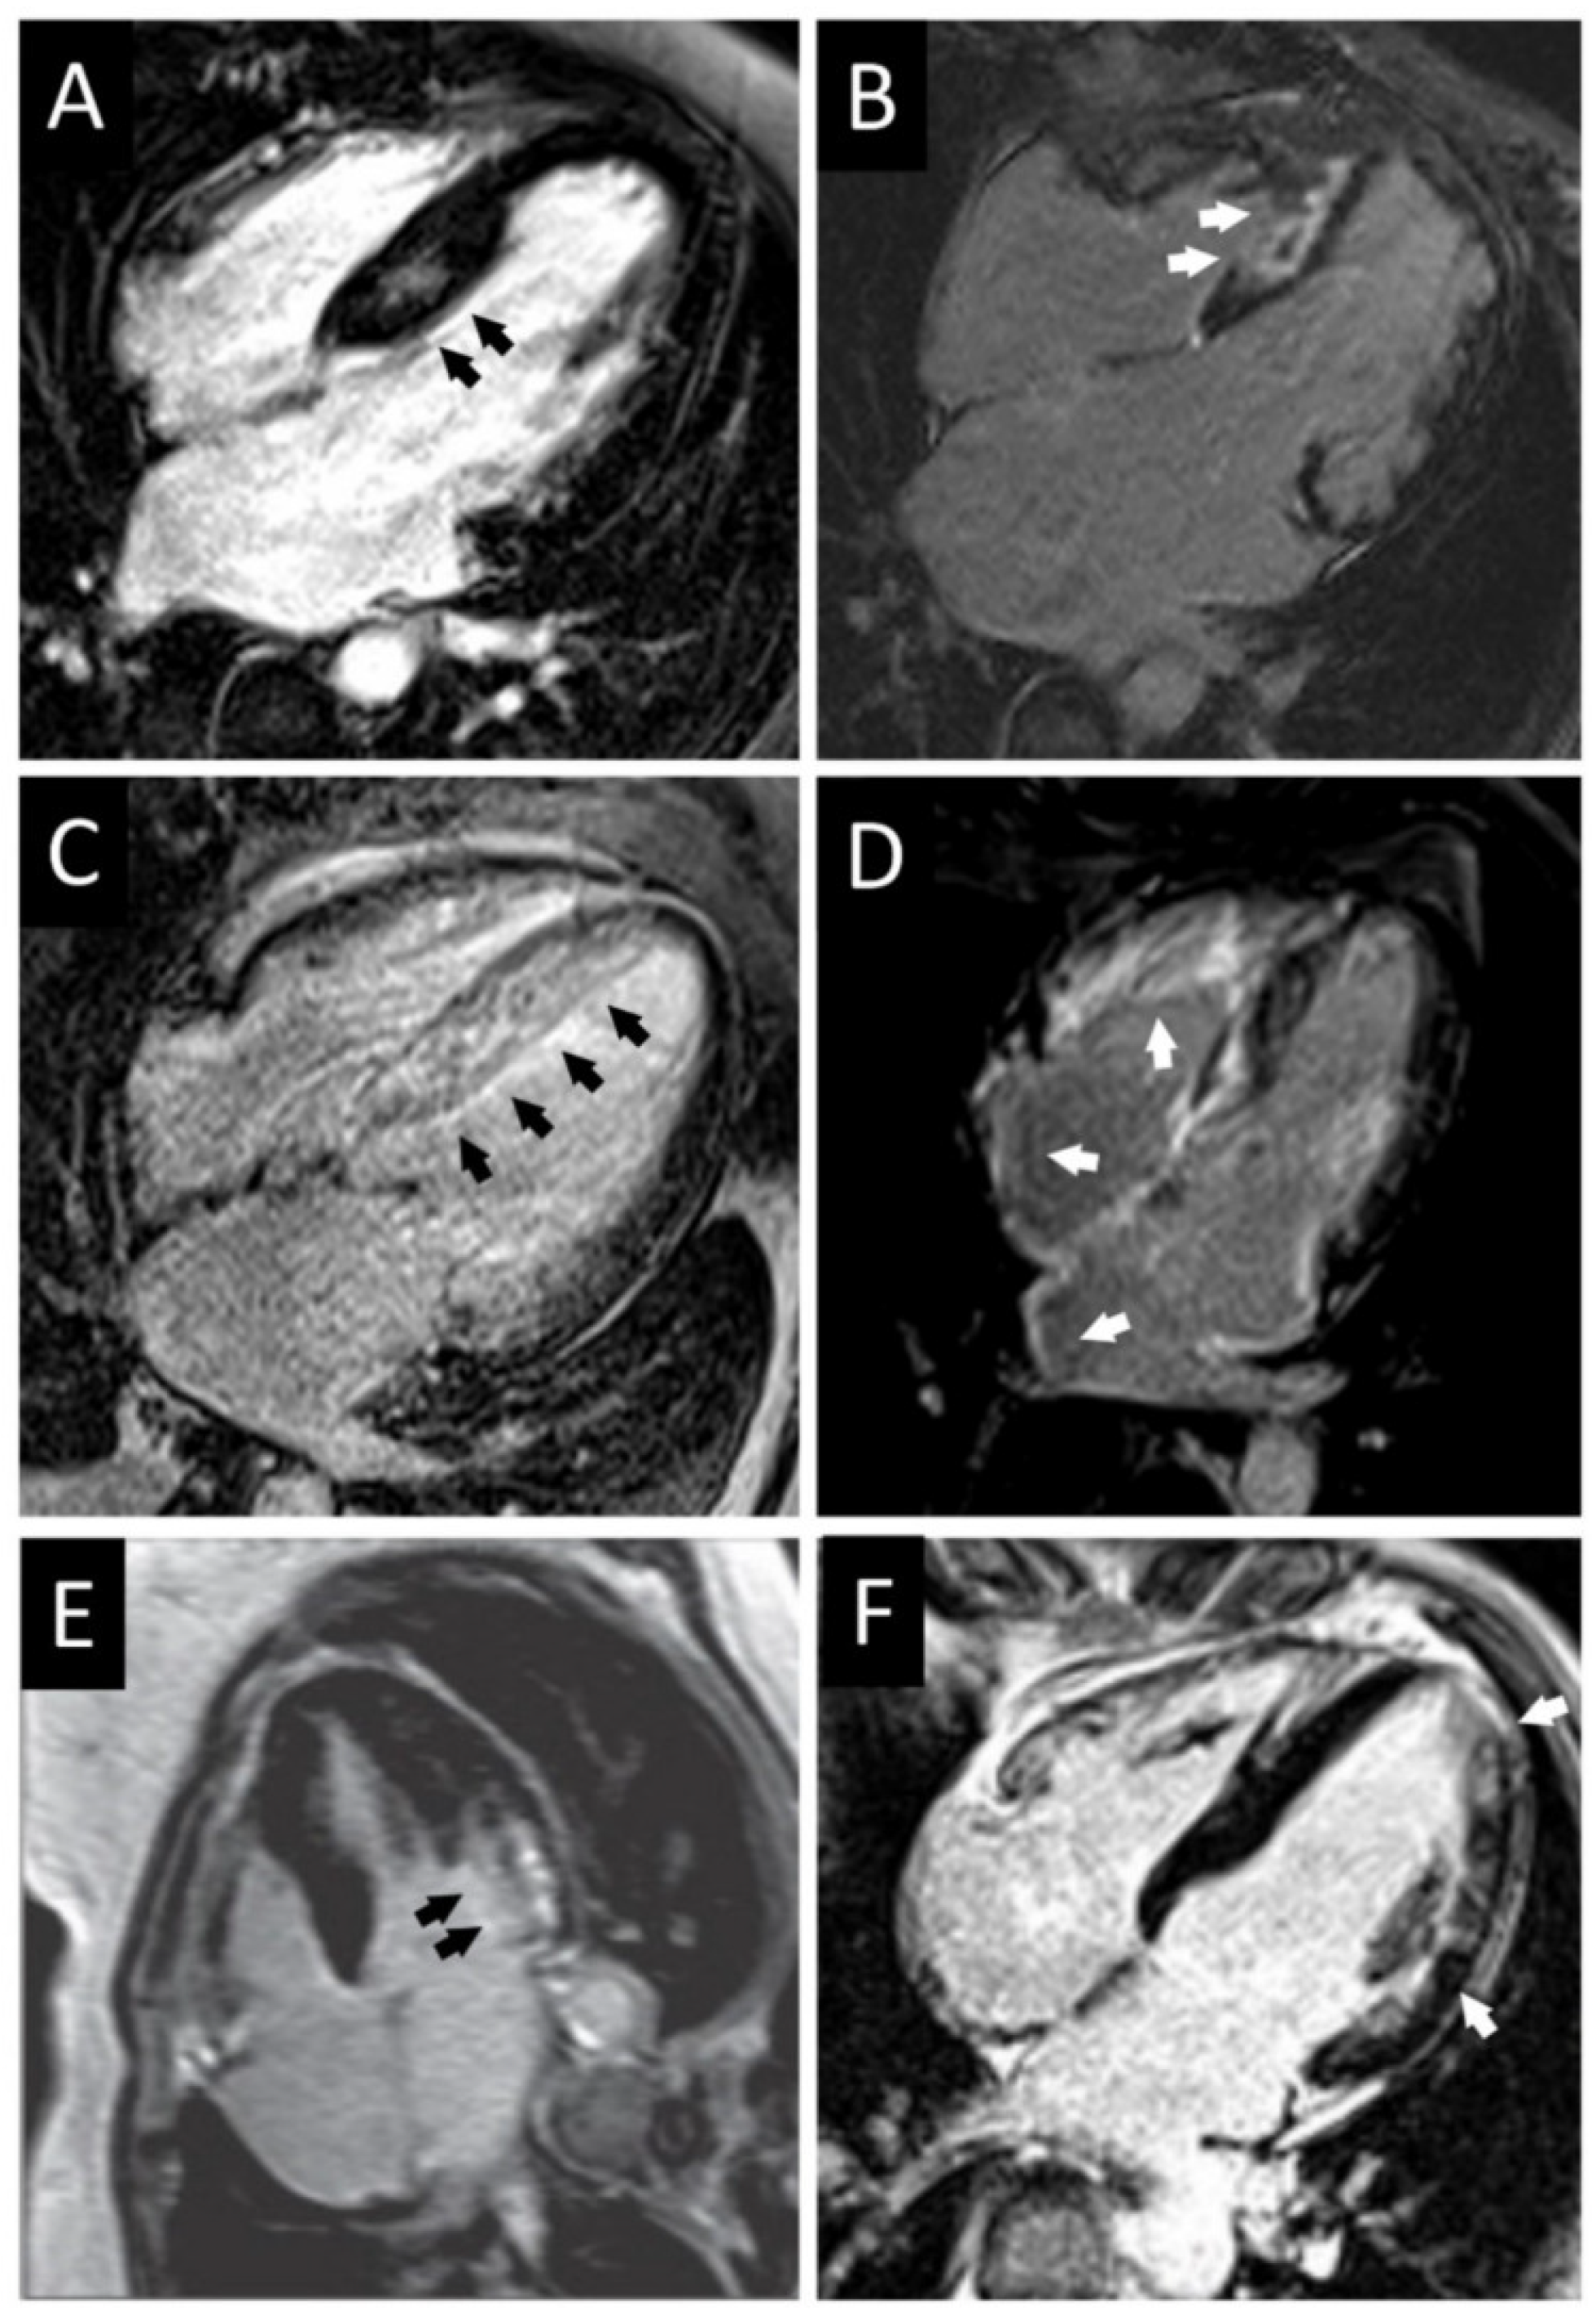

3.1. CMR Evaluation of Apical Hypertrophic Cardiomyopathy

3.2. CMR Evaluation of Focal Hypertrophic Cardiomyopathy

3.3. CMR Evaluation of Midventricular Obstruction

3.4. CMR Evaluation of Apical Aneurysm